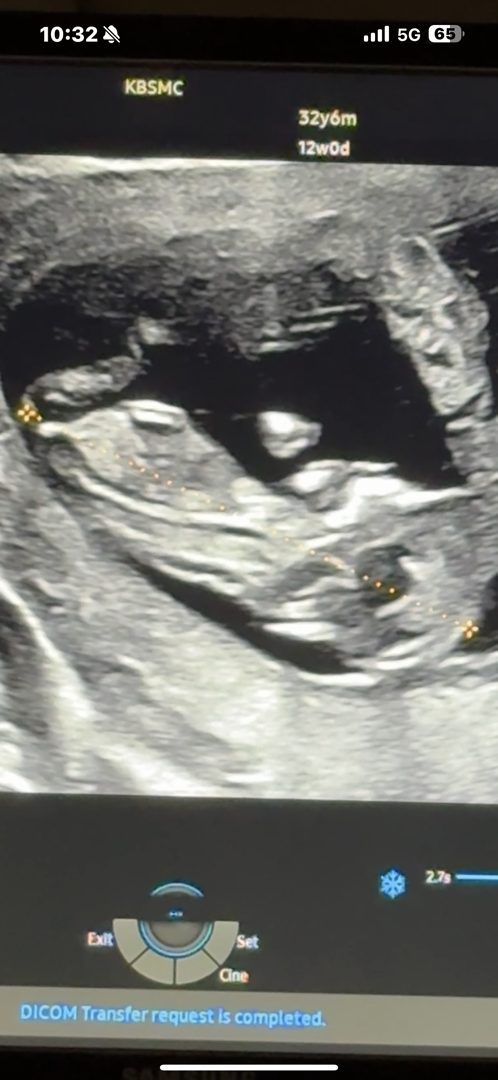

12주 0일 각도법 확인 부탁드려요🥹

각도법 전문가님들,, 어떠신가효,,, 궁금합미댜,,, 이 사진으로 알 수 있는 것일까여..